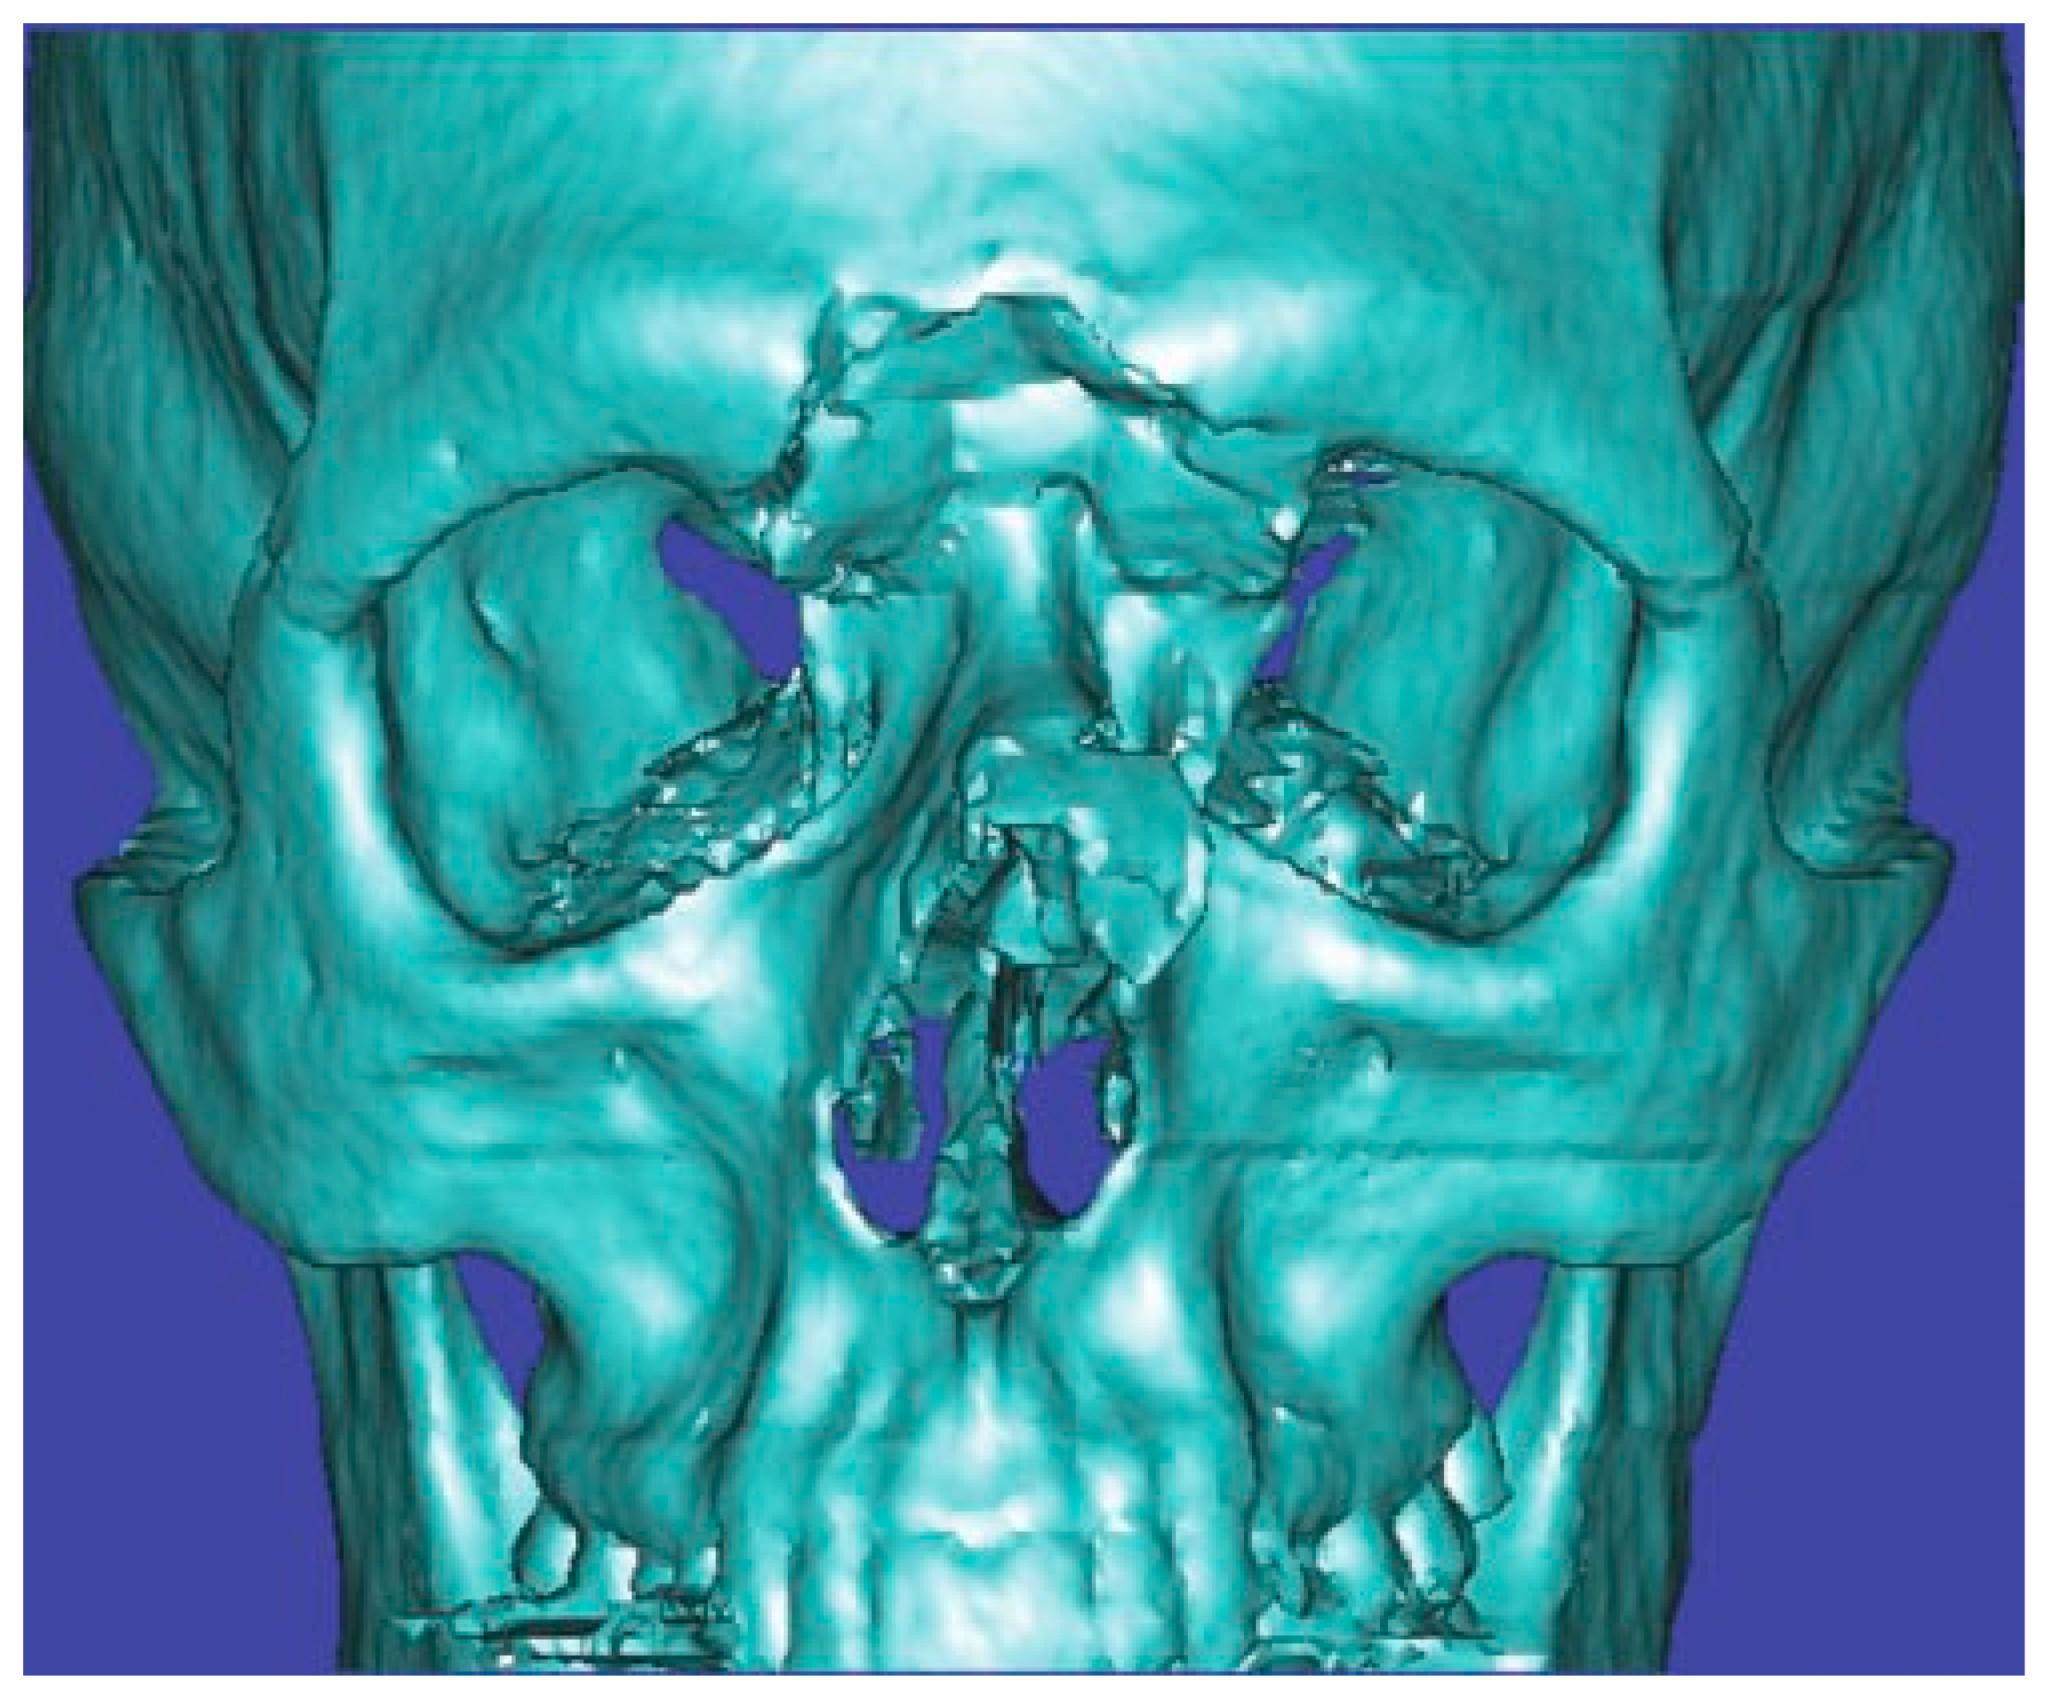

A thin-cut (1.0 to 1.5 mm) axial, coronal, and sagittal computed tomography (CT) scan is the radiological gold standard for diagnosis of frontal sinus fractures. Axial images provide the best information about the anterior and posterior tables (Figure 2); coronal images are used to assess the sinus floor and orbital roof (Figure 3). Sagittal reconstructions can be useful in assessing the patency of the frontal recess (Figure 4), and three-dimensional recon- structions may help to visualize the external contour deformity seen less clearly with two-dimensional cuts alone (Figure 5).

Figure 5.

Three-dimensional computed tomography scan of a frontal sinus fracture. The three-dimensional reconstruction can be helpful in delineating the location of fragments to be located intraoperatively as well as for patient/family education.